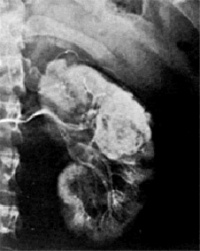

2.X线造影术为诊断肾癌的主要手段

(1)X线平片:X线平片可以见到肾外形增大轮廓改变偶有肿瘤钙化在肿瘤内局限的或广泛的絮状影亦可在肿瘤周围成为钙化线壳状尤其年轻人肾癌多见

(2)静脉尿路造影静脉尿路造影是常规检查方法由于不能显示尚未引起肾孟肾盏未变形的肿瘤以及不易区别肿瘤是否肾癌肾血管平滑肌脂肪瘤肾囊肿所以其重要性下降必须同时进行超声或CT检查进一步鉴别但静脉尿路造影可以了解双侧肾脏的功能以及肾盂肾盏输尿管和膀胱的情况对诊断有重要的参考价值

(3)肾动脉造影:肾动脉造影可发现泌尿系统造影未变形的肿瘤肾癌表现有新生血管动静脉瘘造影剂池样聚集(Pooling)包膜血管增多血管造影变异大有时肾癌可不显影如肿瘤坏死囊性变动脉栓塞等肾动脉造影必要时可向肾动脉内注入肾上腺素正常血管收缩而肿瘤血管无反应 在比较大的肾癌选择性肾动脉造影时亦可随之进行肾动脉栓塞术可减少手术中出血肾癌不能手术切除而有严重出血者可行肾动脉栓塞术作为姑息性治疗